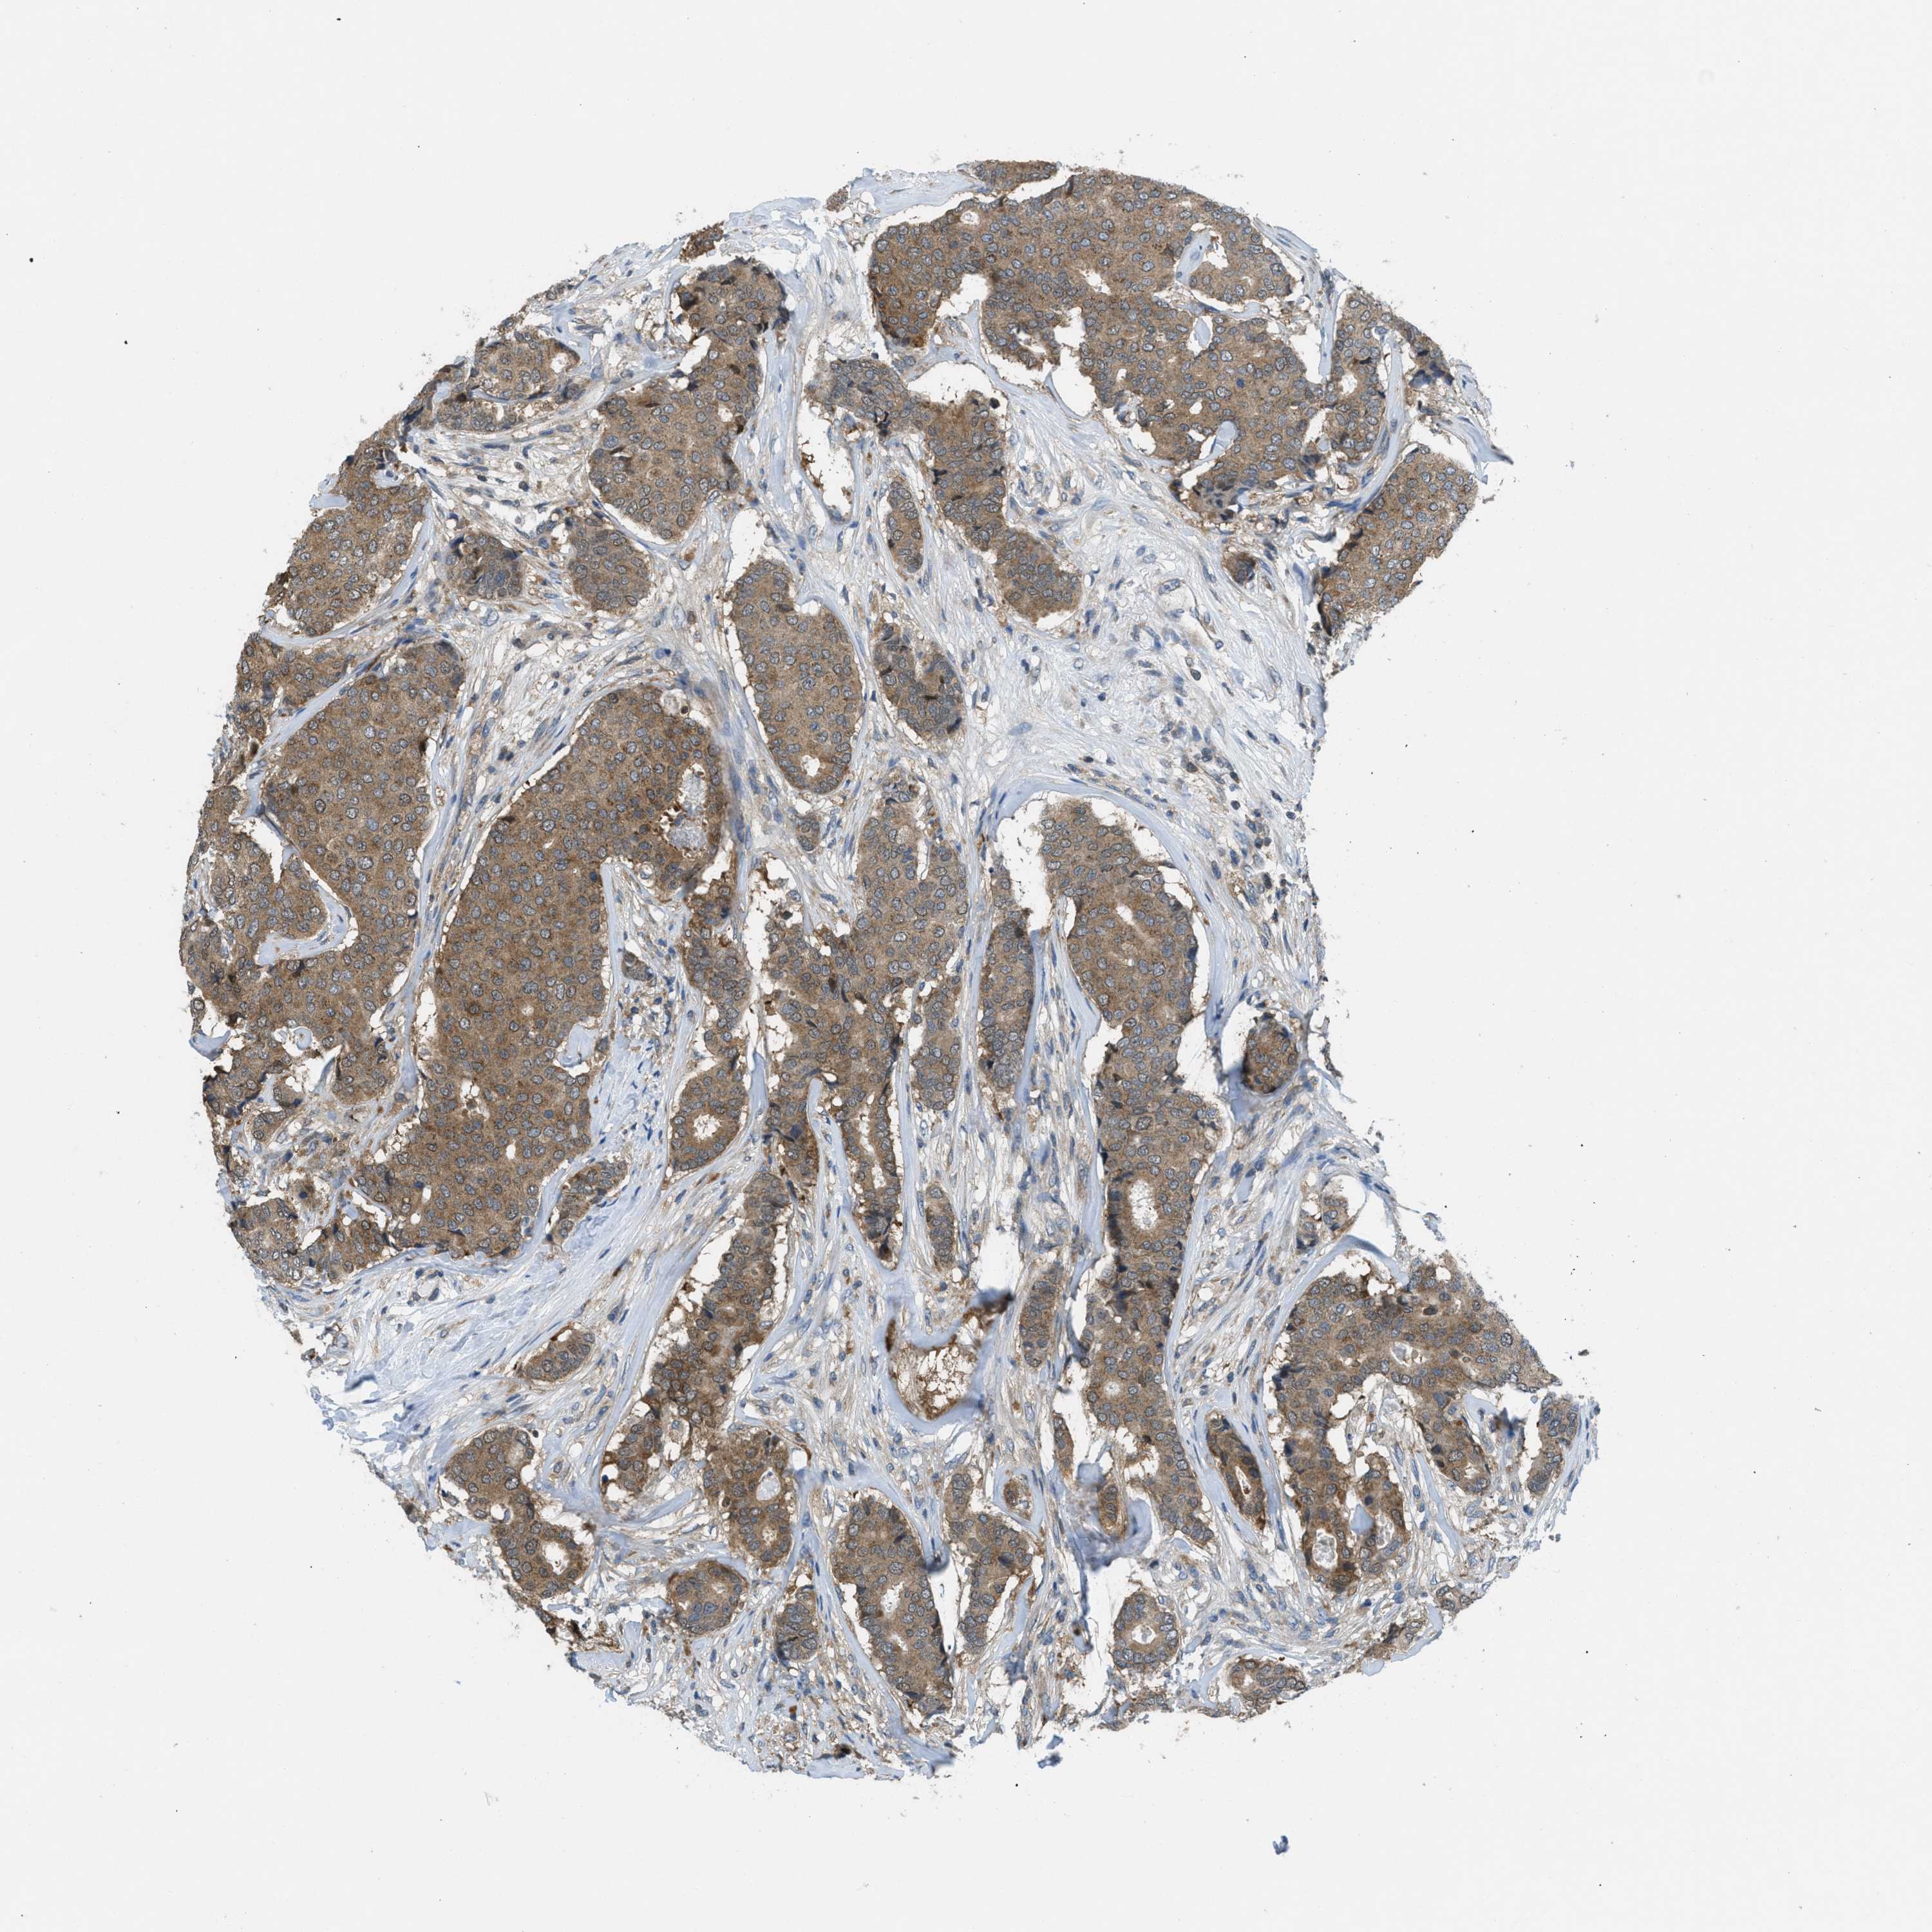

CANCER BREAST CANCER Show tissue menu

BRCA TCGA BRCA VALIDATION PROTEIN EXPRESSION